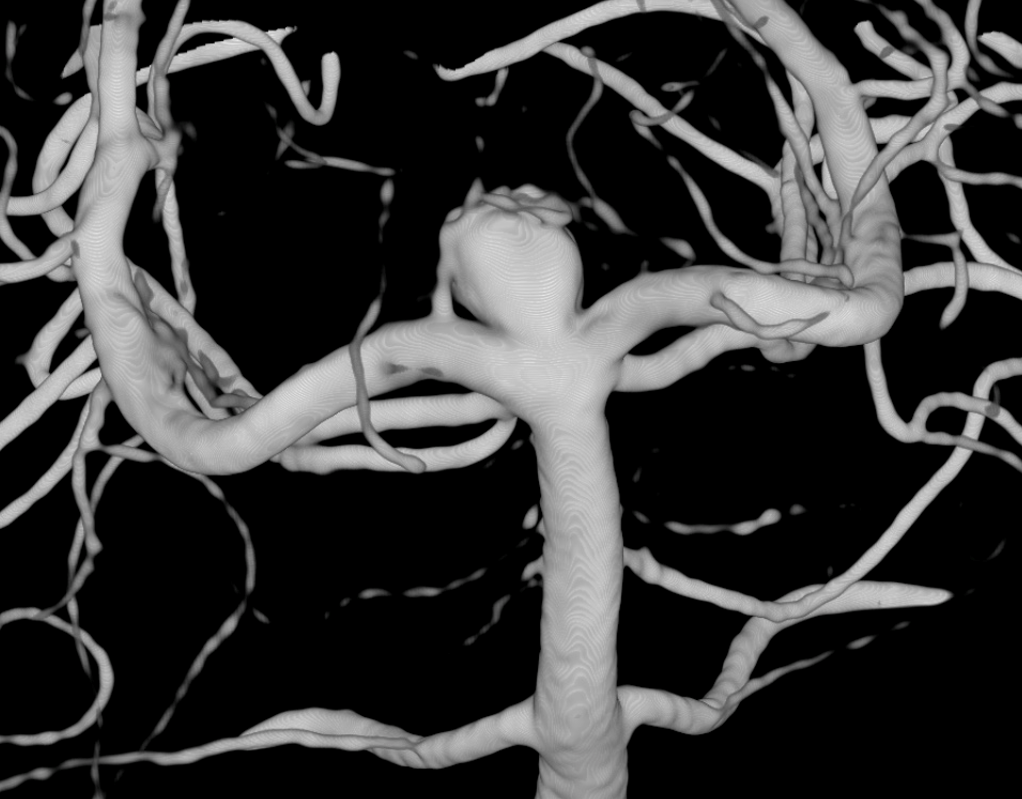

Basilar Bifurcation

Basilar tip aneurysm. A Percheron artery originating from right P1 is already evident.

3D (5 seconds) acquisition. In this case, all 3D and Vaso-CT acquisitions have been made with manual bilateral vertebral artery injection.

Below is Vaso-CT before Artisse. 22 cm FOV, 20 second acquisition. Bilateral pure contrast (300 mg/ml)Â manual injection with 20 ml syringes. Thin MIP reconstruction. No further reconstruction. The Percheron artery is well recognizable.

2 mm MIPs reconstructions